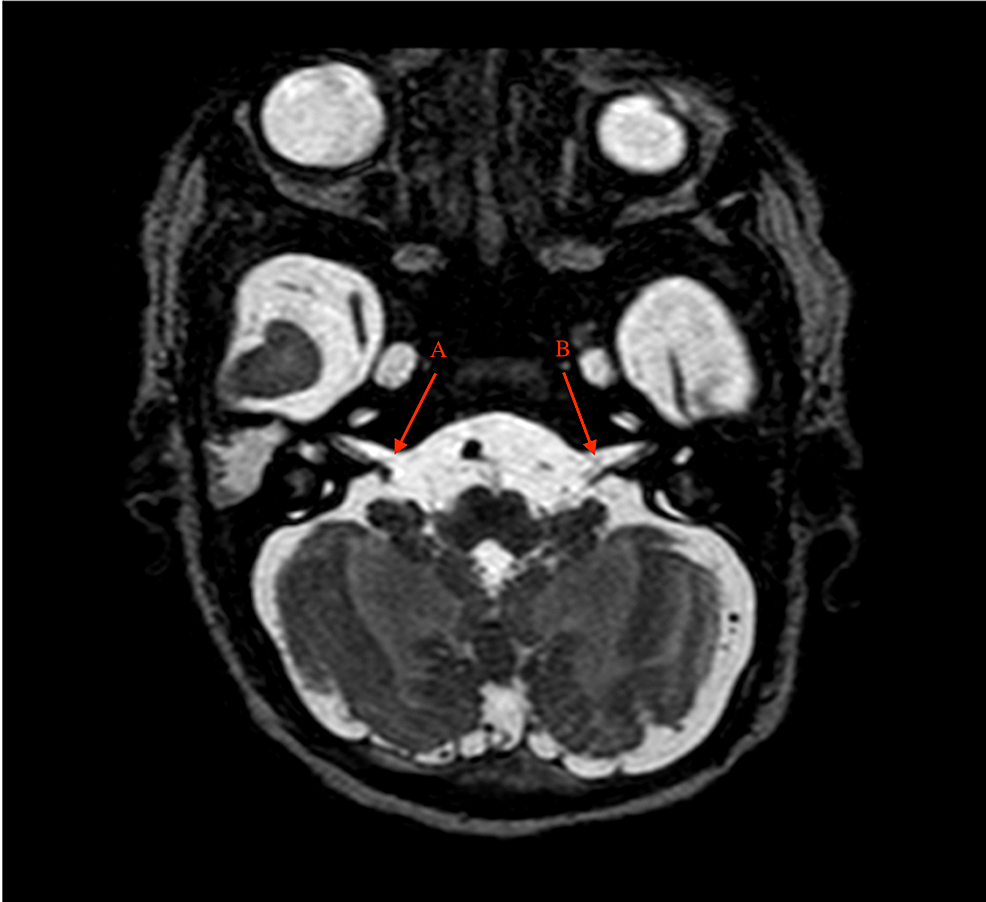

Pupil-Sparing Cranial Nerve III Palsy After Intranasal Cocaine . . .

Three days after medicinal, intranasal cocaine for treatment of a cluster headache, the patient presented with a cranial nerve III palsy with spontaneous resolution in 4 months without any . . .